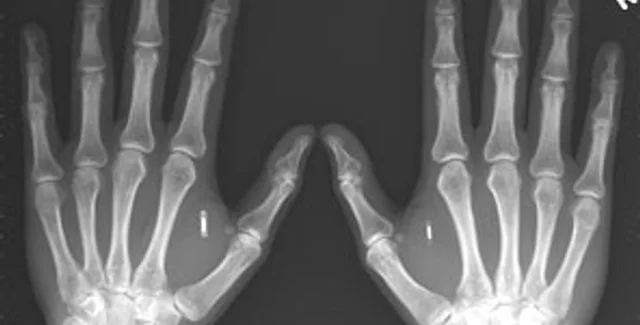

Ученым из Технологического института штата Джорджия удалось создать искусственные кости, которые обладают важным качеством: они способны «срастаться» с иными тканями организма, такими как сухожилия и мускулы.

Новые кости обещают стать причиной небольшой революции в сфере травматологии. Они созданы посредством генной инженерии: фактически, полимерный материал был искусственно совмещен с клетками кожи. Лабораторные опыты показали, что эта методика позволяет достичь успеха. В ближайшее время новая технология будет проходить испытания на животных.

Ранее Пентагон официально анонсировал создание нового Института регенеративной медицины при Министерстве обороны США, который должен будет заняться изучением технологии применения и получения стволовых клеток, а также созданием комплексных систем для восстановления кожи, мышечных и костных тканей. В отдаленной перспективе планируется воссоздавать и целые фрагменты тела - пальцы, нос, уши и т. д.